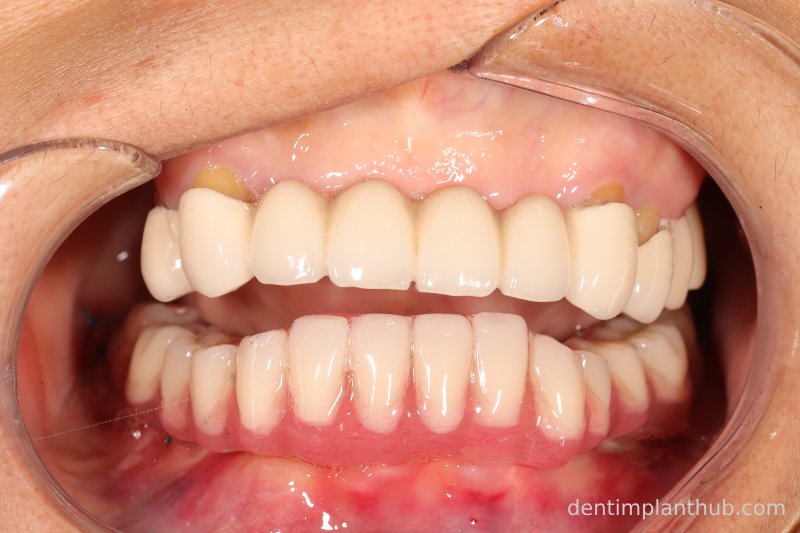

7/6/24 Mandibular preparation for wearing a fixed prosthesis supported by a maroon bridge

Intraoral photographs after putting it on

Photo of temporary crown worn into the mouth on the day of surgery, 7 June '24